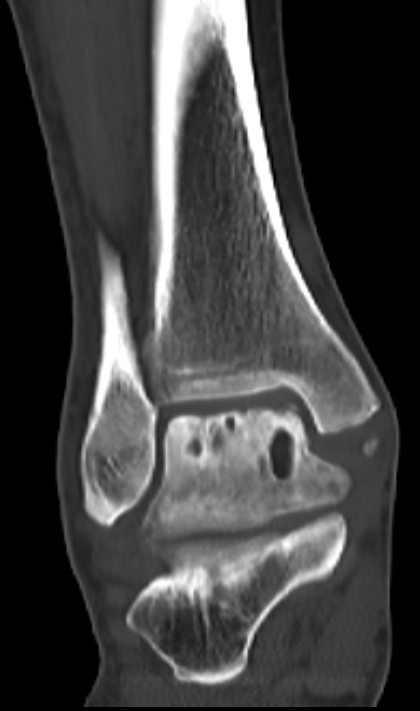

第二位是54岁的大哥,“脚脖子”痛了3年,检查发现只有部分距骨出了问题。

术前CT

针对这种局部病变,团队用了3D打印部分距骨置换术。

这种手术不用大动,只换病变的那部分距骨,尽量保住健康的关节组织,创伤小,术后恢复起来也能快一点。